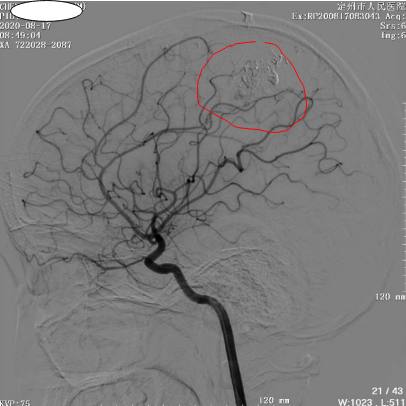

近日,小雷再次入院复查脑血管造影,影像中动静脉畸形团完全不显影。